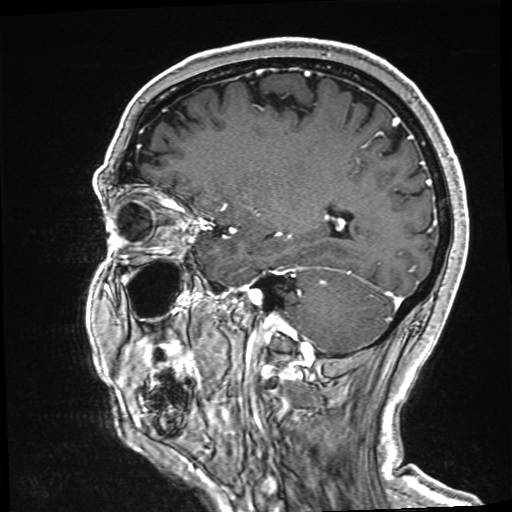

Refer to caption

Figure 2: Illustration of the preprocessing steps for extracting the initial low-dose subtraction image 𝐳~LDsubscript~𝐳LD\tilde{\mathbf{z}}_{\mathrm{LD}}over~ start_ARG bold_z end_ARG start_POSTSUBSCRIPT roman_LD end_POSTSUBSCRIPT from the pre-contrast 𝐱PCsubscript𝐱PC\mathbf{x}_{\mathrm{PC}}bold_x start_POSTSUBSCRIPT roman_PC end_POSTSUBSCRIPT and low-dose 𝐱LDsubscript𝐱LD\mathbf{x}_{\mathrm{LD}}bold_x start_POSTSUBSCRIPT roman_LD end_POSTSUBSCRIPT image. The top images in the steps show the transformed low-dose image while the bottom images visualize the effects on the subtraction image.

To compute the subtraction images 𝐳{LD,SD}subscript𝐳LDSD\mathbf{z}_{\{\mathrm{LD},\mathrm{SD}\}}bold_z start_POSTSUBSCRIPT { roman_LD , roman_SD } end_POSTSUBSCRIPT from a pre-contrast 𝐱PCsubscript𝐱PC\mathbf{x}_{\mathrm{PC}}bold_x start_POSTSUBSCRIPT roman_PC end_POSTSUBSCRIPT and CE 𝐱{LD,SD}subscript𝐱LDSD\mathbf{x}_{\{\mathrm{LD},\mathrm{SD}\}}bold_x start_POSTSUBSCRIPT { roman_LD , roman_SD } end_POSTSUBSCRIPT image pair, we perform the preprocessing pipeline illustrated in Figure 2. First, the brain region 𝐛{0,1}n𝐛superscript01𝑛\mathbf{b}\in\{0,1\}^{n}bold_b ∈ { 0 , 1 } start_POSTSUPERSCRIPT italic_n end_POSTSUPERSCRIPT is extracted by an affine registration of an atlas brain towards the pre-contrast image 𝐱PCsubscript𝐱PC\mathbf{x}_{\mathrm{PC}}bold_x start_POSTSUBSCRIPT roman_PC end_POSTSUBSCRIPT to minimize the effects of motion artifacts from facial regions in the subsequent steps. Second, the itk-elastix library is used to co-register the low-dose 𝐱LDsubscript𝐱LD\mathbf{x}_{\mathrm{LD}}bold_x start_POSTSUBSCRIPT roman_LD end_POSTSUBSCRIPT or standard-dose 𝐱SDsubscript𝐱SD\mathbf{x}_{\mathrm{SD}}bold_x start_POSTSUBSCRIPT roman_SD end_POSTSUBSCRIPT images to the corresponding pre-contrast images. Third, each scan is coarsely normalized by mapping its 95%percent9595\%95 % intensity percentile of the brain region to 1111. This coarse alignment of the intensity values is refined by a radiometric registration step computing a scalar to minimize a robust distance as performed in [9].

Let us denote these initial subtraction images by 𝐳~{LD,SD}subscript~𝐳LDSD\tilde{\mathbf{z}}_{\{\mathrm{LD},\mathrm{SD}\}}over~ start_ARG bold_z end_ARG start_POSTSUBSCRIPT { roman_LD , roman_SD } end_POSTSUBSCRIPT. We further processed them to normalize the noise level within the images, which is often spatially varying in parallel imaging [31]. Since the contrast signal is positive in the subtraction images, we use the negative values in the brain region to roughly estimate the noise levels σLD,σSDsubscript𝜎LDsubscript𝜎SD\sigma_{\mathrm{LD}},\sigma_{\mathrm{SD}}italic_σ start_POSTSUBSCRIPT roman_LD end_POSTSUBSCRIPT , italic_σ start_POSTSUBSCRIPT roman_SD end_POSTSUBSCRIPT of the low-dose and standard-dose subtraction image, respectively. Then, we mask out potential contrast-enhancing pixels and artifacts by removing pixels that are outside of ±2σ{LD,SD}plus-or-minus2subscript𝜎LDSD\pm 2\sigma_{\{\mathrm{LD},\mathrm{SD}\}}± 2 italic_σ start_POSTSUBSCRIPT { roman_LD , roman_SD } end_POSTSUBSCRIPT. On this masked subtraction image, we estimate the local mean 𝐦{LD,SD}nsubscript𝐦LDSDsuperscript𝑛\mathbf{m}_{\{\mathrm{LD},\mathrm{SD}\}}\in\mathbb{R}^{n}bold_m start_POSTSUBSCRIPT { roman_LD , roman_SD } end_POSTSUBSCRIPT ∈ blackboard_R start_POSTSUPERSCRIPT italic_n end_POSTSUPERSCRIPT and standard deviation 𝐬{LD,SD}nsubscript𝐬LDSDsuperscript𝑛\mathbf{s}_{\{\mathrm{LD},\mathrm{SD}\}}\in\mathbb{R}^{n}bold_s start_POSTSUBSCRIPT { roman_LD , roman_SD } end_POSTSUBSCRIPT ∈ blackboard_R start_POSTSUPERSCRIPT italic_n end_POSTSUPERSCRIPT using large Gaussian filter kernels with a standard deviation of 16161616 pixels. These local noise characteristics are then used to correct field-inhomogeneities and normalize the noise level within the subtraction images, such that